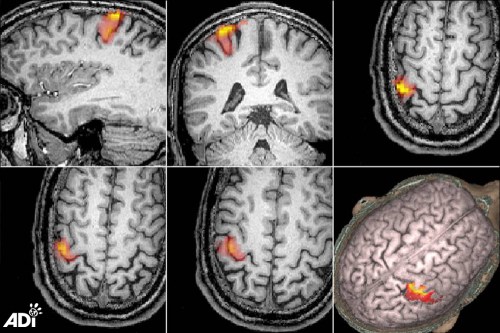

Advanced human brain imaging

Primates are frequently used in brain research and they suffer enormously. There are fundamental differences between species, so adoption of new techniques in neuroscience is vital.

For a decade, the Lord Dowding Fund (LDF) funded the neuroimaging group at the Aston Brain Centre (ABC), headed by Professor Paul Furlong, which is now a world-leading Centre of Excellence for brain development and imaging studies. The ABC engages in a wide range of research activities studying human behaviour and brain function. The group works to establish how new techniques may be used to replace animal experiments. Projects include vision, neurodevelopment and clinical research, cognition and pharmacokinetics (drug characteristics).

The team examined the effect of a drug, Zolpidem, on a stroke patient. Zolpidem is typically used to treat insomnia and belongs to a class of drugs called sedative hypnotics. Several studies have shown that the drug can provide transient improvement in the condition of patients, which was repeated when the drug was re-administered. The work at Aston involved MRI and MRS scans of the patient, designed to characterise both the anatomical and chemical damage caused by the stroke. Changes in brain circulation and activity were identified and administration of the drug showed improved circulation in the affected half of the brain.

Another study, that could not possibly be conducted with any reliability in animals, involves the differences in the brain when participants are critical or reassuring towards themselves. Self-criticism has been strongly correlated with a range of conditions such as depression, anxiety and eating disorders, and “self-reassurance” is inversely associated with the same conditions. As little is known about the neurophysiology of these internal processes, the group used a new fMRI task to investigate. Results indicated self-criticism was linked to activity in the areas of the brain which are connected to error processing and resolution, and behavioural inhibition. Self-reassurance was linked to the brain areas responsible for compassion and empathy towards others. This work is useful for showing the neural basis for certain mood disorders and cannot be carried out on animals. Studies such as these show the elegance and real scientific relevance of cutting-edge technologies.